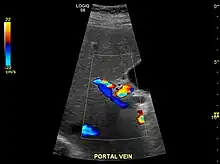

Imaging

Ultrasound is routinely used in the evaluation of cirrhosis.[34] It may show a small and shrunken liver in advanced disease. On ultrasound, there is increased echogenicity with irregular appearing areas.[51] Other suggestive findings are an enlarged caudate lobe, widening of the fissures and enlargement of the spleen.[52] An enlarged spleen, which normally measures less than 11–12 cm (4.3–4.7 in) in adults, may suggest underlying portal hypertension.[53] Ultrasound may also screen for hepatocellular carcinoma and portal hypertension.[34] This is done by assessing flow in the hepatic vein.[54] An increased portal vein pulsatility may be seen. However, this may be a sign of elevated right atrial pressure.[55] Portal vein pulsatility are usually measured by a pulsatility indices (PI).[54] A number above a certain values indicates cirrhosis (see table below).